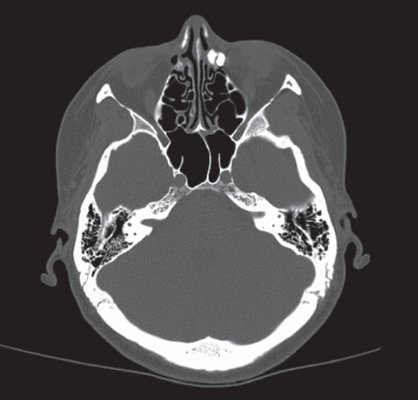

На серии снимков при мультиспиральной компьютерной томографии слёзных путей было видно, что контрастное вещество полностью заполняло слёзный мешок, но в полость носа не поступало (рис. 1). Было принято решение о выполнении эндоскопической эндоназальной дакриоцисториностомии с применением полупроводникового диодного лазера в контактном режиме (2017). В послеоперационном периоде жалоб на слезотечение не было, при промывании жидкость свободной струёй прошла в нос. Спустя год после эндоскопической операции пациентка вновь отметила слезотечение, периодическое гноетечение слева. Был поставлен диагноз: «Рецидив хронического гнойного дакриоцистита слева». С учётом уже выполненных ранее двух хирургических вмешательств по поводу хронического гнойного дакриоцистита травматической этиологии и наличия травмы лицевого скелета черепа в анамнезе, было принято решение о проведении ревизионной операции с постановкой биканаликулярного силиконового стента под контролем этапов операции с помощью навигационного оборудования.

Рис. 1. Мультиспиральная компьютерная томография полости носа, околоносовых пазух с контрастированием слёзных путей

Fig. 1. Multispiral computer tomography of nasal cavity, paranasal sinuses with contrast-enhancement of lacrimal pathways